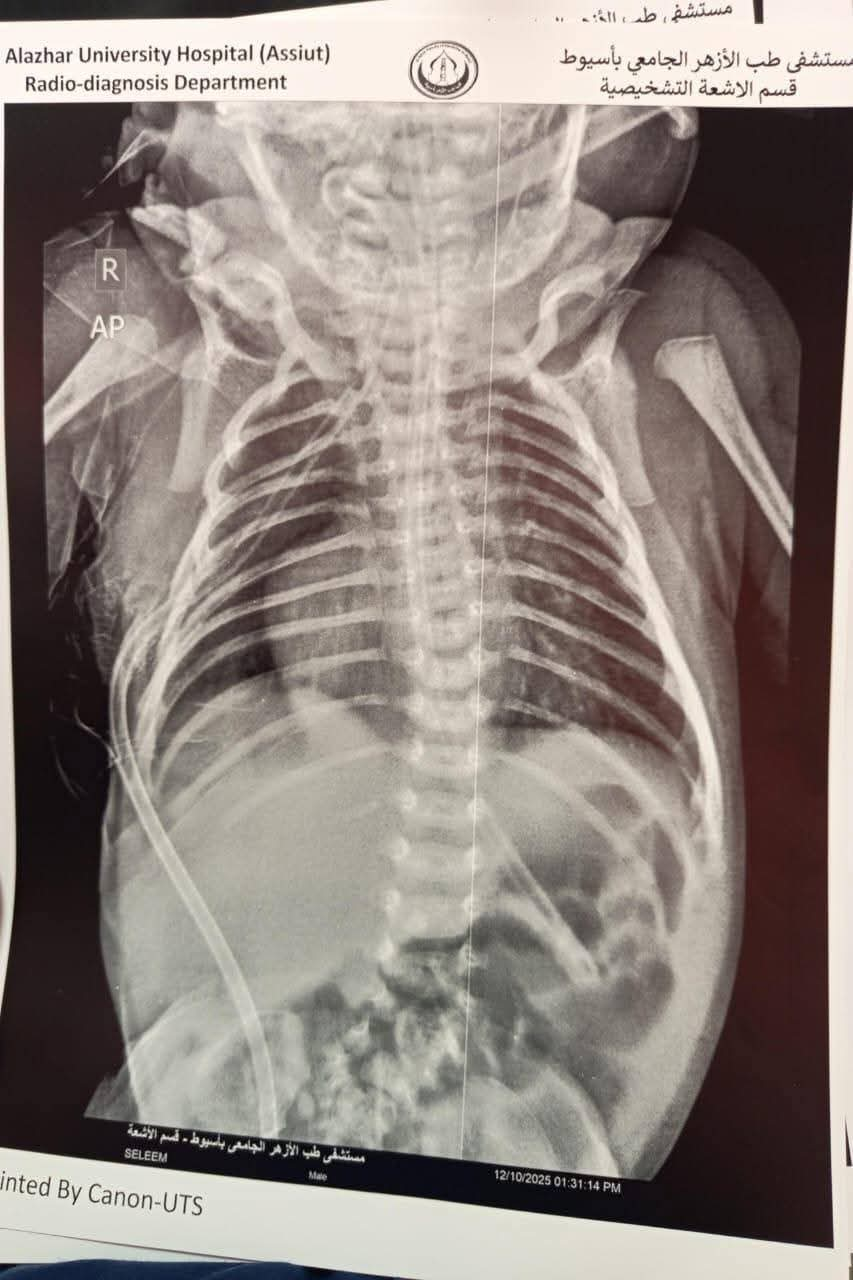

وأوضح عميد كلية الطب ورئيس مجلس إدارة مستشفى الأزهر الجامعي بأسيوط أن نتائج الفحوصات أكدت وجود انسداد كامل بالمريء وناسور بحجم كبير بين المريء والقصبة الهوائية، مما استدعى التدخل الفوري لإنقاذ حياة الطفل. وتم تجهيز غرفة العمليات لإجراء الجراحة التي تُعد من أعقد جراحات الأطفال، وتتطلب دقة ومهارة عالية.

وأكد عميد كلية الطب أن الفريق الطبي تمكّن، خلال 4 ساعات من العمل فصل الناسور تمامًا عن القصبة الهوائية، وإعادة توصيل المريء بنجاح، إلى جانب تركيب قسطرة وريدية مركزية لضمان استمرار تقديم العلاج اللازم للرضيع عقب الجراحة. وخرج الطفل من غرفة العمليات في حالة مستقرة.